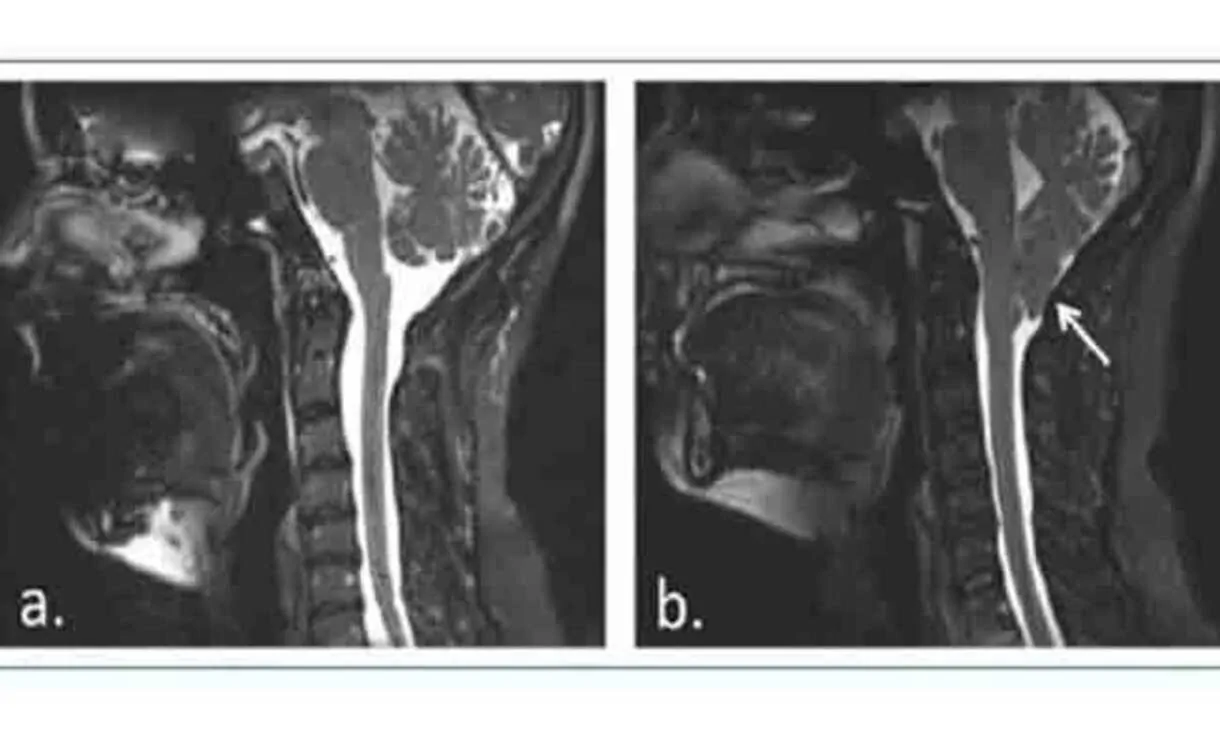

A Malformação de Chiari tipo I implica uma herniação caudal das amígdalas cerebelosas de aproximadamente 5 mm abaixo do foramen magnum, que geralmente não se acompanha de descida do tronco encefálico ou do quarto ventrículo nem de hidrocefalia, mas sim de siringomielia.

A siringomielia é causada pela formação de cavidades ou cistos (siringe ou syrinx) cheios de líquido dentro da medula espinhal, que podem expandir-se lentamente, causando um dano progressivo à medula espinhal e hipertensão intracraniana devido à pressão exercida por esse líquido.

Menina diagnosticada com Malformação de Chiari tipo I, com siringomielia, submetida a cirurgia aos 12 anos de idade.